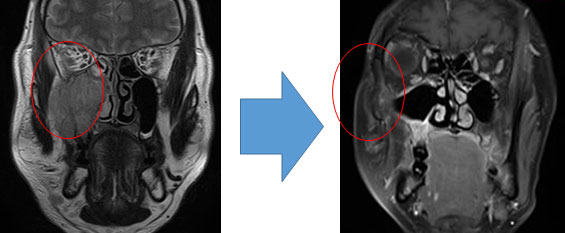

成人に発症した横紋筋肉腫

術前化学療法により、右副鼻腔の腫瘍は著明に縮小している。